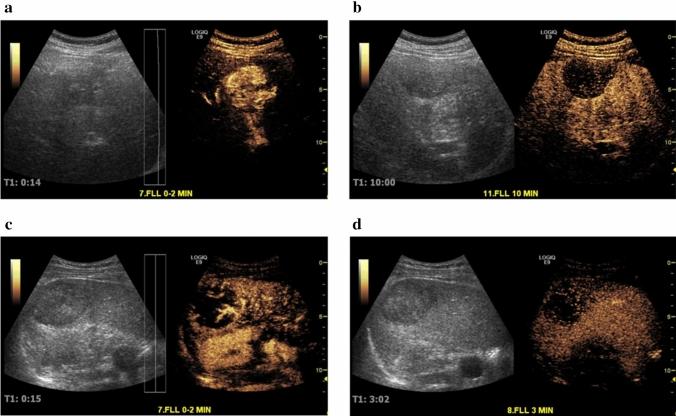

To assess the respective diagnostic value of Sonazoid™ and SonoVue® for characterizing FLLs as benign or malignant and the corresponding safety.

This prospective Phase 3 study was conducted at 17 centres in China and Korea (May 2014 to April 2015); 424 patients (20 to 80 years) with at least 1 untreated focal liver lesion (FLL) (< 10 cm in diameter) underwent a contrast-enhanced ultrasound (CEUS) examination (218 received Sonazoid of 0.12 μL microbubbles/kg; 206 received SonoVue of 2.4 mL). Three independent blinded readers evaluated pre- and post-contrast images characterising the FLLs as benign or malignant.

Sonazoid-enhanced and SonoVue-enhanced ultrasound provided a statistically significant improvement in specificity for all 3 readers comparing to unenhanced ultrasound (for Sonazoid: p = 0.0093, < 0.0001, 0.0011; for SonoVue: p = 0.002, 0.03, 0.12, respectively). Difference in accuracy improvement between the 2 groups was within the pre-specified non-inferiority margin of 20% for all 3 readers (6.1%, 95% CI: - 5.0 to 17.2; - 7.5%, 95% CI: - 18.4 to 3.5; - 0.3%, 95% CI: - 11.3 to 10.7). The diagnostic confidence level for all 3 readers increased with post-contrast images relative to pre-contrast images. Both contrast agents were well tolerated.

Results showed a similar efficacy for Sonazoid™ and SonoVue® in diagnosing FLLs as benign or malignant, and underlined the benefit of CEUS imaging over unenhanced ultrasound imaging in reaching a confident diagnosis without having to refer patients for additional imaging exams.